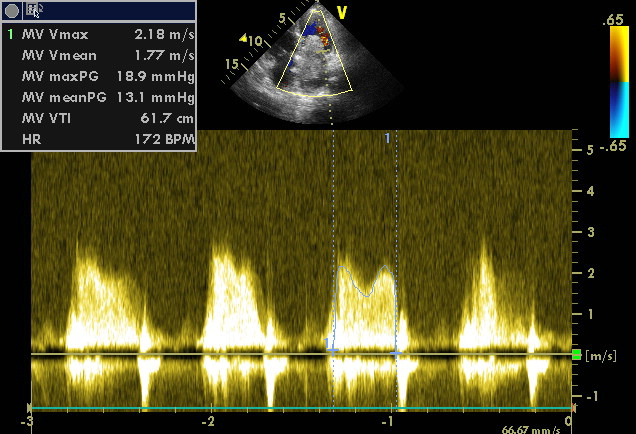

5. Рис.2 | |

| Тема | ||

| Тип | Прочее | |

Посмотреть

(57KB)